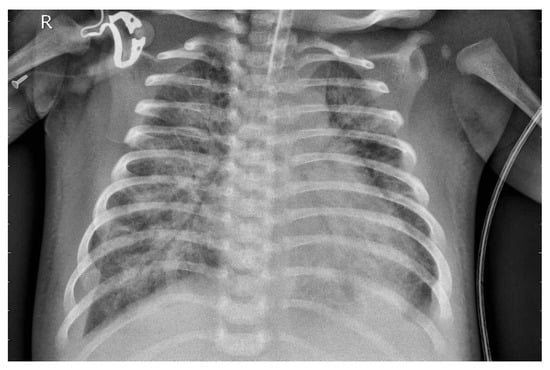

3.1. Dataset

3.2. Preprocessing